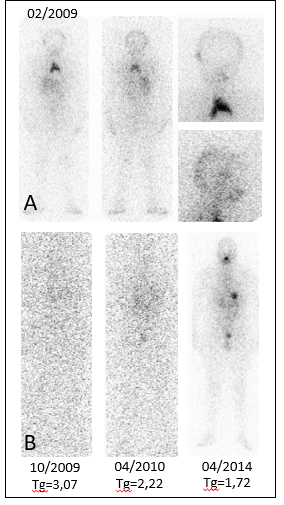

On posttreatment scintigraphy intense upper mediastinal uptake is noted, corresponding to probable thymic tissue. (Figure 2A) which is an uncommon cause of false-positive that might be considered as lung or mediastinal nodes metastases [3].

Subsequent serial negative (last Tg 1.72 ng/ml) (Figure 2B).

Figure 2